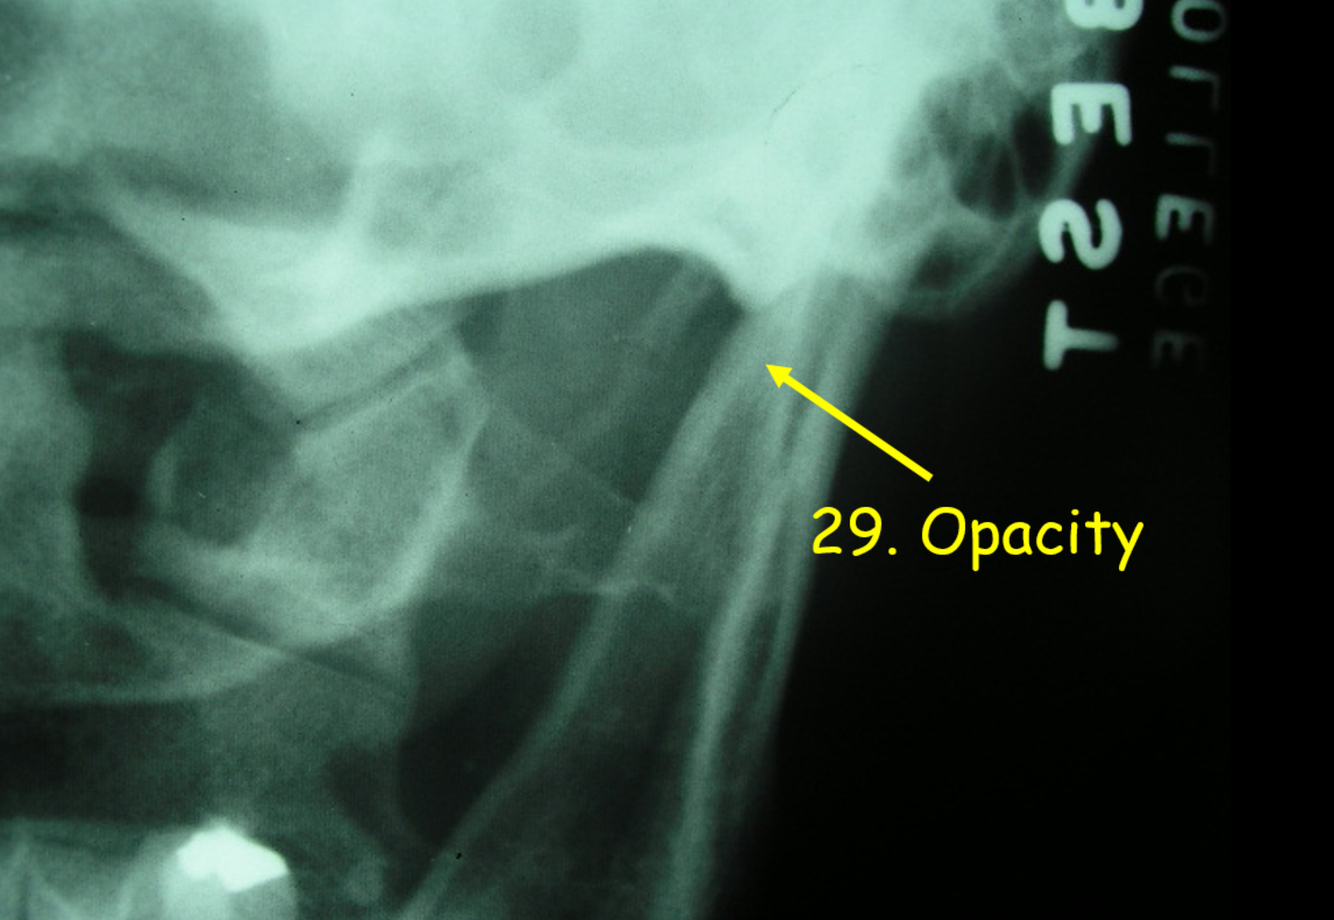

5

Q

What is 29?

A

transverse process